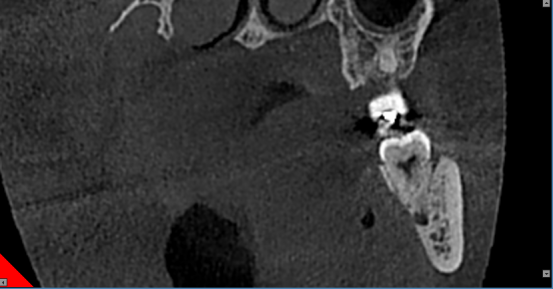

根管和牙周治疗过程中,提供牙根位置、角度、是否牙裂病变及下颌管、牙周围组织高清图像,以便于分辨治疗每个细节,做出精确诊断以及有效治疗方案。